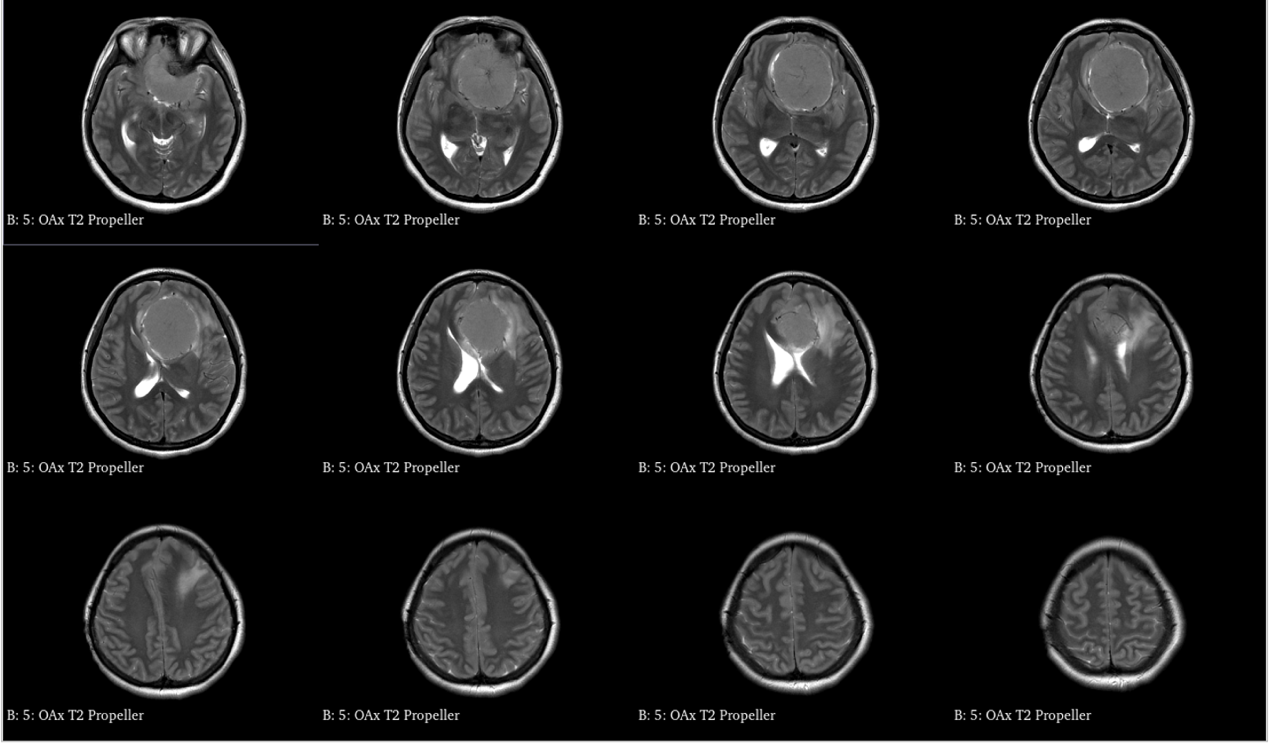

青年女性,因“左眼失明10个月,头痛3个月”就诊我院。

入院诊断:颅内占位病变(前颅窝底)脑膜瘤?;左眼失明;鼻炎

前颅窝底脑膜瘤常起源于前颅底筛骨筛板处的硬膜,瘤体多为双侧生长,少数为偏侧生长,女性稍多于男性。肿瘤可累及鸡冠和蝶骨平台的任何区域,是前颅窝肿瘤中最多见的一种。因为肿瘤位于前颅窝底,额叶在功能上属于“哑区”,患者就诊发现肿瘤时瘤体多已巨大。主要症状可有颅内压增高症状、视力减退、癫痫以及精神症状等。该患者主因“左眼失明10个月,头痛3个月”就诊。术中采用双额冠状开颅,左侧为主,由于肿瘤体积巨大,术中切除少许薄层额叶脑组织,边离断基底、边瘤内减压,分块切除肿瘤,最终探查肿瘤基底主要位于鸡冠、筛板、蝶骨平台、鞍结节、前床突处硬膜,术中见肿瘤供血主要来源于前颅窝底硬膜及大脑前动脉分支,术中仔细辨认供血动脉、过路血管,大脑前动脉及其分支保护完好,术中见视神经、视交叉受压明显,尤其是左侧视神经已缺血苍白,最终达Simpson II级切除。术者体会,该患者术前行多模态重建,可见瘤表数条粗大的静脉,术中切莫过早离断肿瘤的引流静脉,以防因引流不畅致瘤体肿胀出血;术前行多模态重建,利于鉴别供血动脉、过路血管,早期离断供血动脉更利于肿瘤切除;该类肿瘤基底一般较为广泛,不能盲目离断基底,尤其是近鞍结节处,可以于中线处离断基底,进入第一间隙后向两侧探查并保护视神经,待充分缩小瘤体看清楚毗邻的血管神经后再将其完全切除;术毕做好多层颅底重建以防脑脊液漏。另外,该患者术前左眼失明已达10个月,术后第1天即有光感,术后1月复查左眼视力可达50cm内数指,这在临床中非常少见,对于此类病人,不要轻易放弃挽救视力的任何机会。